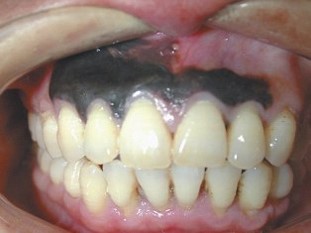

Также для выявления патологии применяются следующие лабораторные и аппаратные методики:

• МРТ, КТ, УЗИ (проводится исследование вторичного поражения областей, в которых расположены регионарные и отдаленные метастазы);

• биопсия, после которой полученный биоматериал направляется в лабораторию для цитологического и гистологического исследования;

• определение наличия мутаций в генах BRAF и C-KIT.

Risunok3.jpg